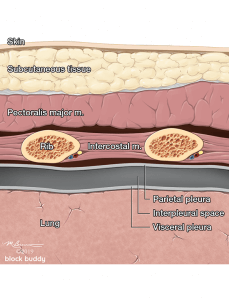

3. Anatomy

Anatomy

- The ribs will appear as convex hyperechoic lines with acoustic shadows.

- Located between the ribs are the hypoechoic intercostal muscles and the smooth, thin hyperechoic pleural line.

- These structures form the “bat sign”: the shadow of the ribs form the wings, while the area between the ribs represents the body.

- The pleural line is comprised of the parietal and visceral pleura, but will appear as a single, thin hyperechoic line.